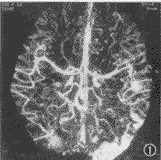

脑血管成像示:(1)55例CTA均可清楚显示1~4级脑血管结构、Willis环和大脑前、中、后动脉主干及其分支情况。(2)脑动静脉畸形12例,其中枕叶3例,颞叶5例,额叶3例,顶叶1例。可见异常增粗迂曲的血管,9例血管呈团状,5例可见增粗的引流血管,5例部分血管有钙化,均可清楚地观察到畸形血管的位置和范围(图1)。(3)动脉瘤2例,清楚地观察到瘤体大小、位置、形态,以及与血管的关系(图2,3)。(4)脑肿瘤19例,其中9例脑膜瘤可见肿瘤邻近血管被推移或包裹,4例可见肿瘤表面有异常血管(图4)。4例胶质瘤和4例转移瘤可见瘤体呈不均匀强化,或不强化,周围有不同程度水肿,肿瘤附近血管被推移(图5);位于第4脑室的室管膜瘤和位于中颅窝蝶骨翼旁的三叉神经瘤可见瘤体呈不同程度强化,室管膜瘤有血管推移。(5)大脑中动脉及分支栓塞3例,2例大脑中动脉主干变窄、变细,远侧方血管变细、变少(图6);1例大脑中动脉顶后分支变细,变窄,远侧方血管较少;(6)脑挫裂伤及脑脓肿可见局部血管有不同程度推移,脑积水以两侧大脑前、中动脉抬高较为明显。

图1 AVM CTA,可见左颞枕叶及右枕叶多发畸形血管